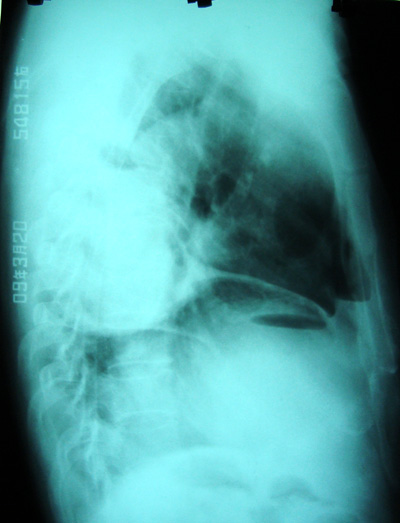

从侧位平片看,有气体影,结合断层考虑膈下脓肿

膈下可见气液平面,结合临床应该考虑膈下脓肿并同侧胸腔积液(脓)

右侧膈肌抬高明显,胸腔内无明显积液,表现为胸膜反应,肝脏周围大量积液,并见多个液气平面。右下肺不均匀密度增高影。结合临床考虑右侧膈下脓肿并腹腔内积液、右下肺并发感染及胸膜反应,节段性肺不张不除外。

右隔下积脓并右侧肺脓肿;右侧液气胸